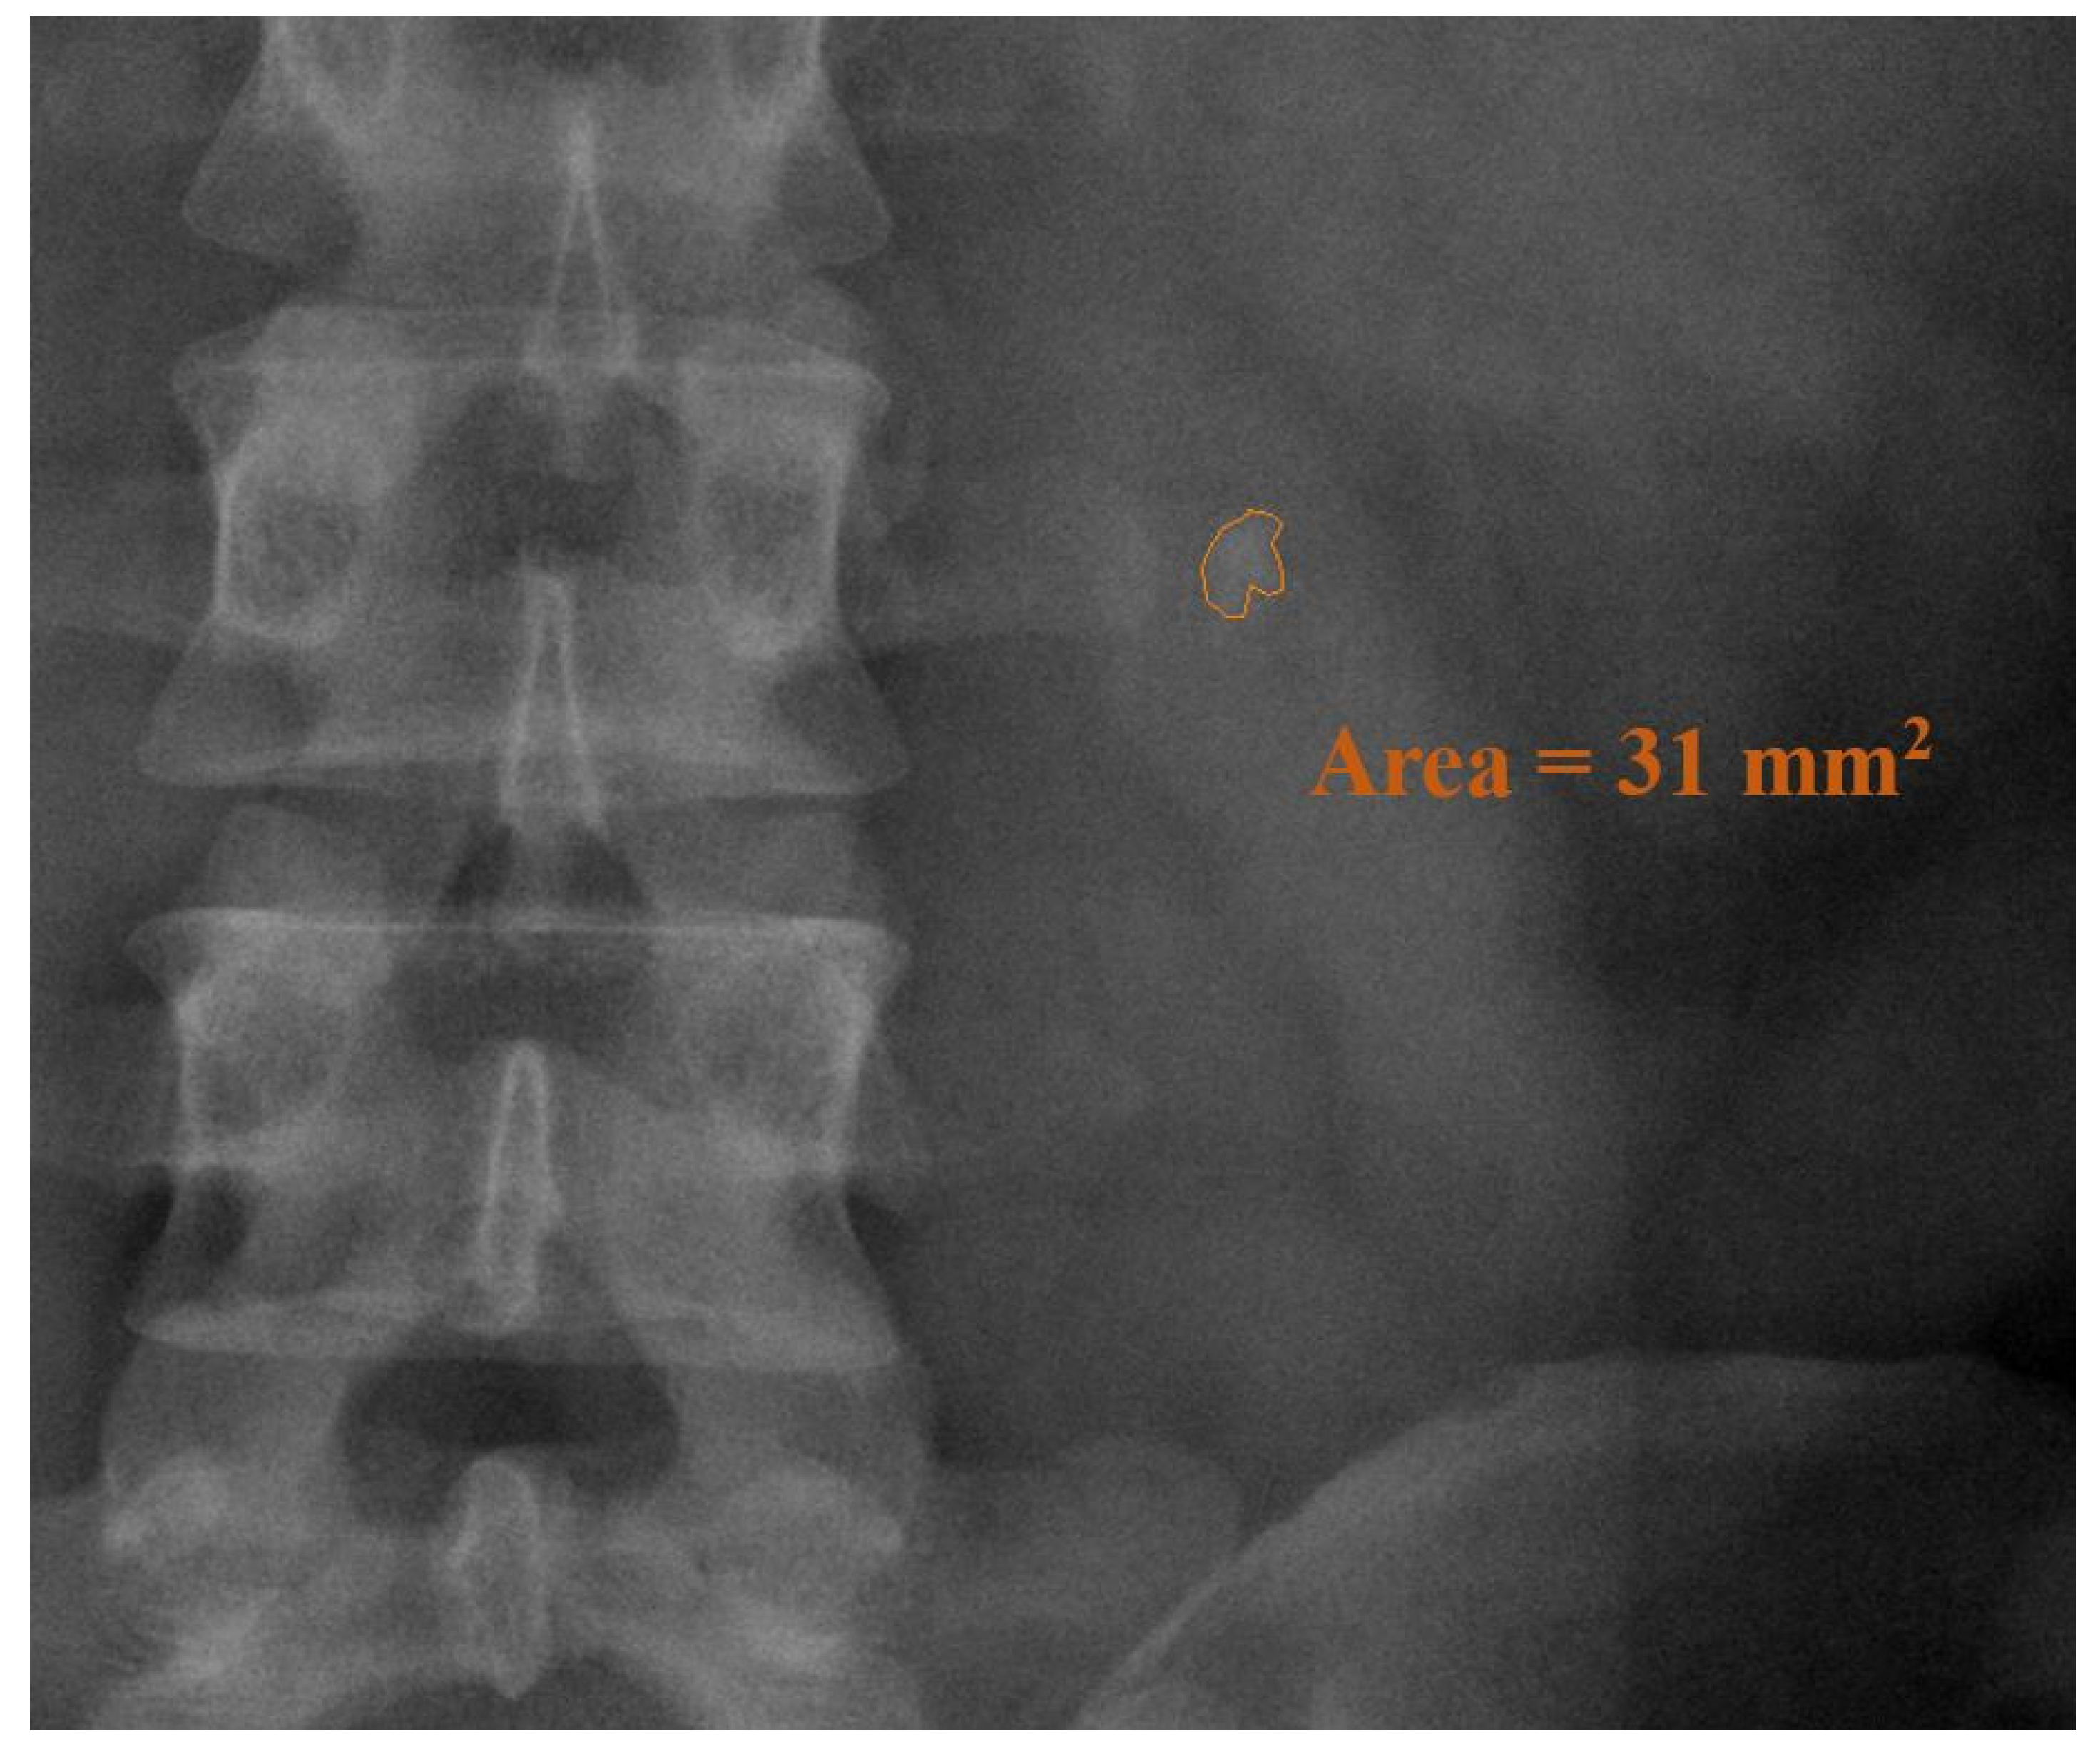

| Mean stone burden, mm2; mean ± SD * | 56.8 ± 60.71 | 48.9 ± 59.23 | 0.199 | |

| Mean stone burden, mm2; mean ± SD 2 | 51.33 ± 58.69 | 48.9 ± 59.24 | 0.722 | |